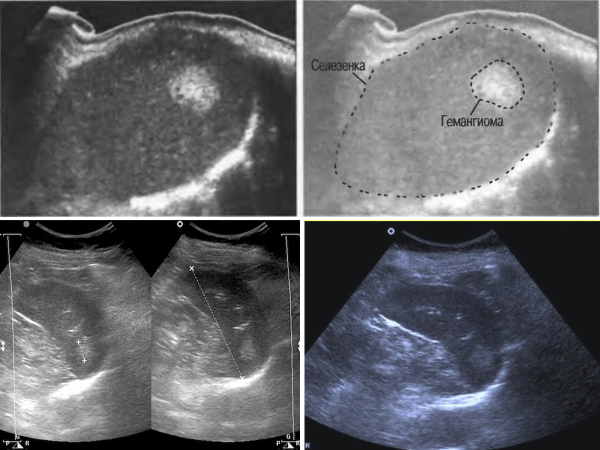

Гемангиома

- Наиболее частая опухоль селезенки (0,3-14% аутопсий).

- Является васкулярной доброкачественной опухолью из кровеносных сосудов.

- Могут быть одиночными и множественными.

- По строению могут быть капиллярными, кавернозными и смешанными.

При УЗИ:

- При капиллярном типе - округлые гиперэхогенные образования с ровным четким четким контуром различных размеров (чаще не более 2 см).

- При кавернозном типе – в структуре определяются гипоэхогенные включения.

- При ЦДК определяется питающая артерия и дренирующая вена.